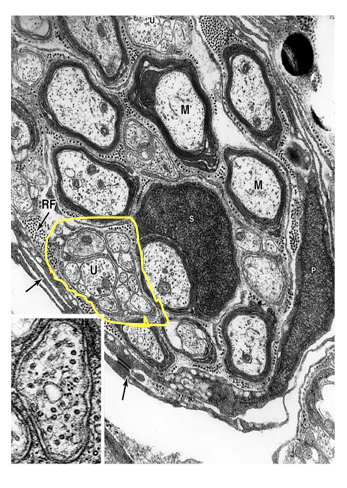

Unmyelinated nerves (PNS)

*may be enclosed in a single invagination of Schwann cell surface

* axon rests in a cleft in the cytoplasm of a Schwann cell, with a single mesoaxon